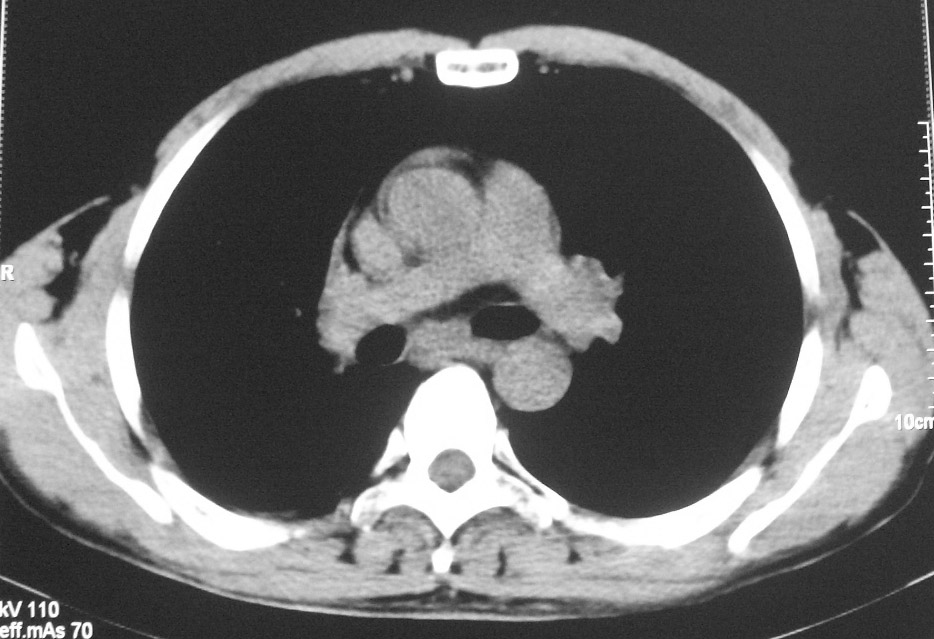

标题: CT5485:[原创]肺部占位请讨论

右肺上叶中央型肺癌并上叶肺不张、纵隔淋巴结肿大

右肺上叶中央型肺癌并上叶肺不张、纵隔淋巴结肿大 。

右肺上叶中央型肺癌并上叶肺不张、纵隔淋巴结肿大.右侧少量胸腔积液。

右肺上叶中央型肺癌并上叶肺不张。

右肺上叶中央型肺癌并上叶肺不张、纵隔淋巴结肿大.

右肺上叶中央型肺癌并阻塞性炎症、阻塞性肺不张……

右上肺癌,肺不张,纵隔淋巴结肿大

右肺上叶中央型肺癌